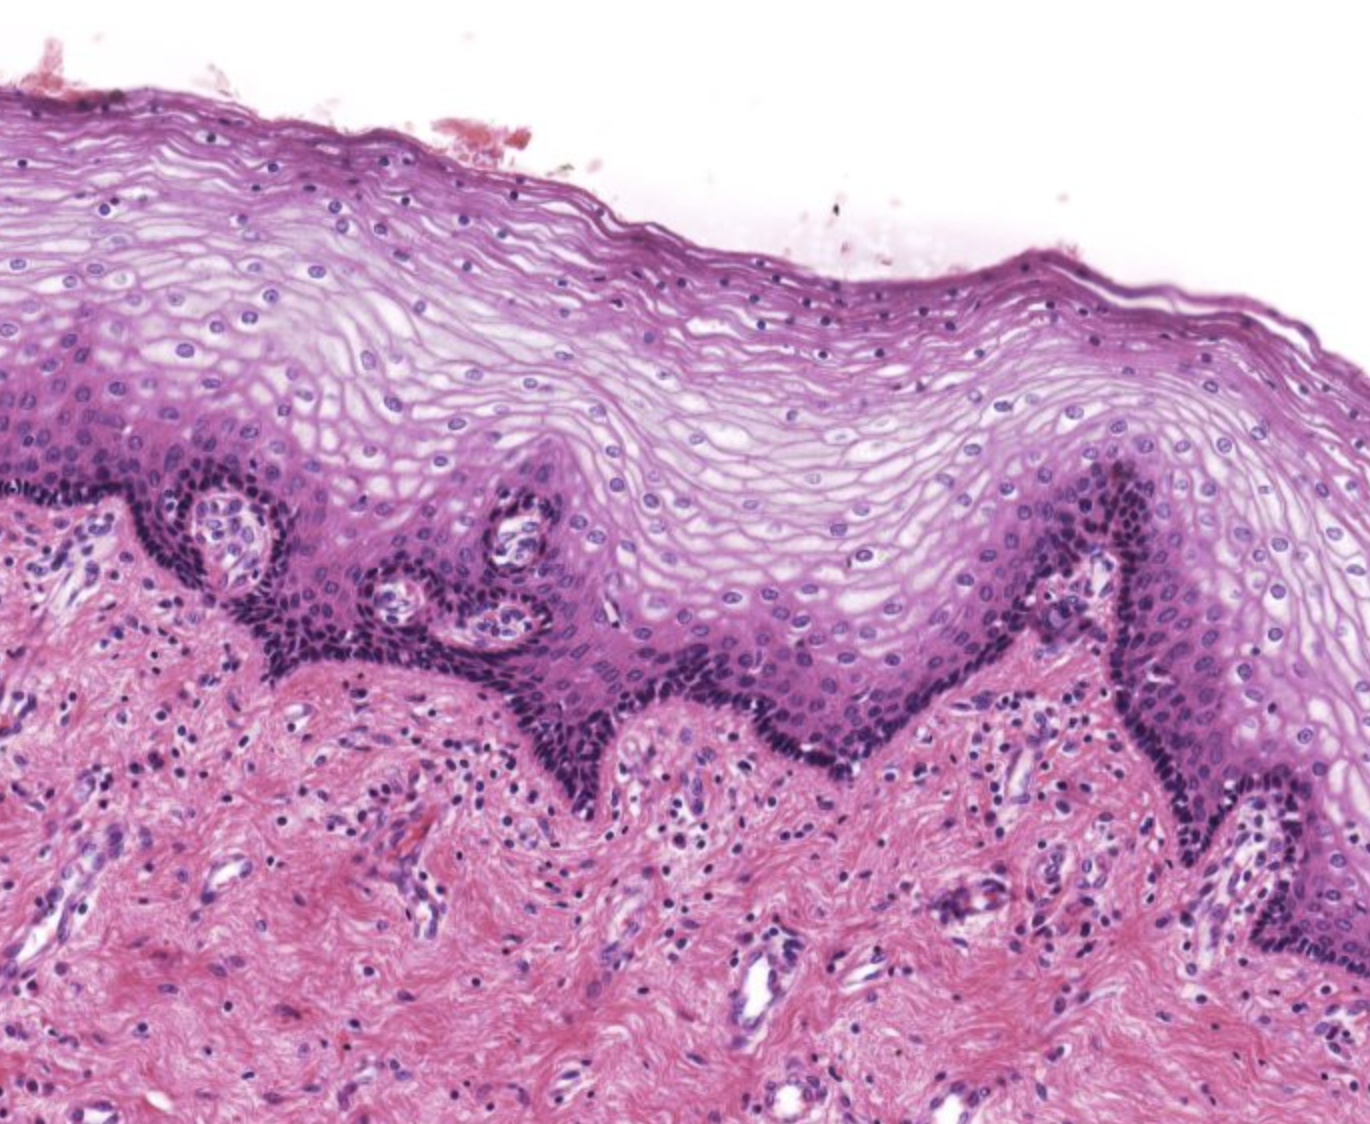

Vagina: Propria submucosa

Epithelium

Describe the connective tissue

Lack of

Additional structures

Epithelium: Non keratinized straitified squamous

Describe the connective tissue: Loose or dense CT

Lack of: Glands

Additional structures: Lymphooid tissue